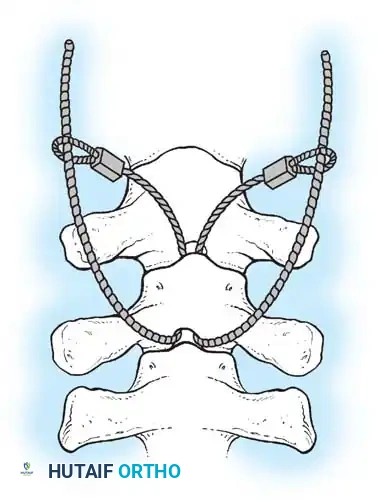

The Hall Technique

The Hall technique offers an alternative method for facet obliteration and grafting, particularly useful in rigid deformities.

Fig. 38-28: The Hall technique of facet fusion, involving sharp excision of the inferior facet and trough creation.

- Sharply amputate the inferior articular facet with a gouge and remove the bone fragment entirely. This exposes the cartilage of the superior facet.

- Remove the exposed cartilage completely with a sharp curet.

- Create a bleeding trough by removing the outer cortex of the superior facet.

- Impact cancellous bone grafts directly into this vascularized trough.

- Complete the procedure with global decortication of the posterior elements.